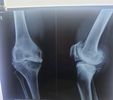

I have seen some of the most complicated and dangerous fracture cases in the past 10+ years. Thus, I always recommend getting fracture treatment as early as possible to prevent serious complications.